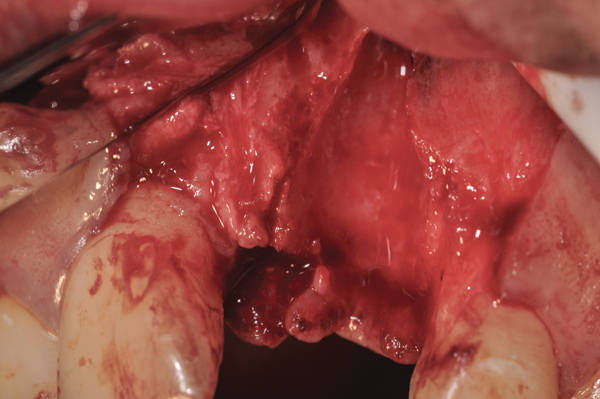

Fig 10. At 3 months postoperative, the flap was elevated demonstrating a restored buccal plate of bone.

Figure 10